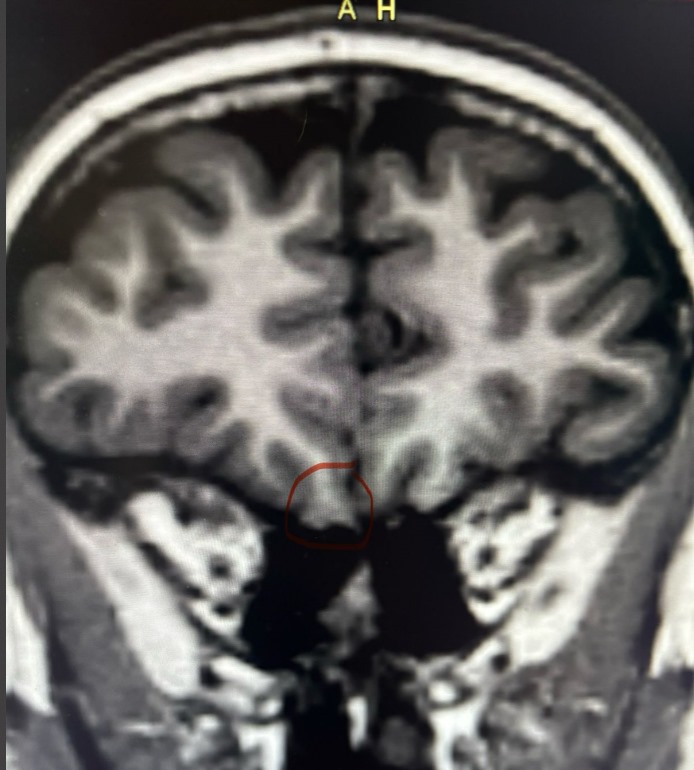

May 19, 2025Long-term monitoring demonstrated no inter-ictal abnormalities during wakefulness and sleep. Similarly, the EEG was normal during ssizures. A confident diagnosis of frontal lobe epilepsy was made, based on careful analysis of the history and the video findings (> 90% seizures in sleep). Multiple MRI scans had been reported as normal. A repeat high resolution 3T MRI scan was reported as normal. Repeated scrutiny eventually disclosed following probable focal cortical dysplasia